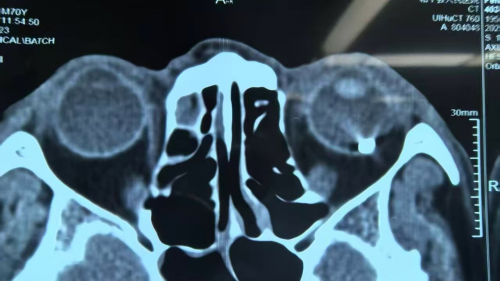

24岁小黄(化名)用不锈钢磨钻机打磨钢管时触碰到电线,飞溅物崩入眼睛,此后眼前黑影飘动、遮挡视线,眨眼、擦眼都无法消除。小黄在当地眼科进行就诊检查,CT影像清晰显示,眼底后部球壁内存在一个呈现点状强回声的金属异物。鉴于当地医疗资源和诊疗条件的局限性,医生建议他前往省内上级专科医院做进一步的治疗。

(小黄术前检查图)

赵铁英院长仔细询问致伤过程,查看此前两家医院的检查报告,还是怀疑异物有铜丝的可能性,以往接诊过铜异物长期在眼内产生化学毒性反应致盲的病例,所以又与特检科何梦宜主任在光学相干断层扫描仪下动态观察异物精确位置和堪入的组织深度。在跟患者充分交代沟通、做好各方面准备后还是决定进行取出手术,以防局部组织包裹粘连。在Alcon3D显微镜下精准微创顺利取出的异物,确定为铜丝。